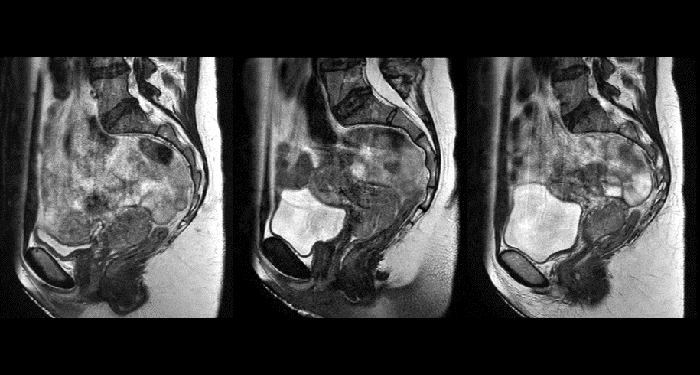

With its exceptional soft-tissue visualization capabilities and wide range of image contrasts, MRI has become a powerful tool to help more precisely define tumor boundaries. This is particularly important as it has been established that there is a high degree of uncertainty in target volume delineation, and it is even reported to represent the largest uncertainty in the entire radiotherapy process for most tumor sites**. Better visualization of the target area and nearby organs-at-risk is a key factor in enhancing target volume delineation. MRI’s expanding role also can be attributed to its functional imaging capabilities, which can inform both target characterization and treatment response.

With its superior soft tissue contrast compared to CT, MRI offers exquisite visualization of tumor boundaries and proximity to nearby critical structures.

The ability to tune contrasts can provide even more valuable information about tumor characteristics and tumor extent to facilitate enhanced delineation, and also provides possibilities for dose boosting strategies. - Functional imaging

Cervical cancer treatment with 3D MRI-guided brachytherapy

Arhus University Hospital at the forefront of MRI guidance in adaptive cervical cancer radiotherapy.